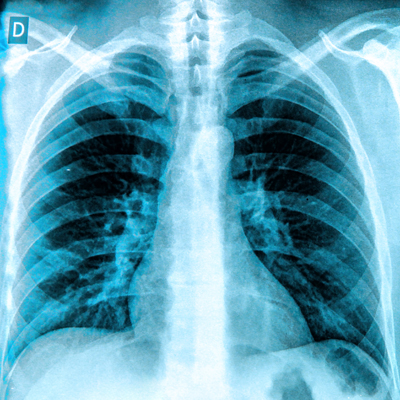

(A, B) Images with true-positive findings. Digital radiographs in (A) a 79-year-old woman with dementia and hypertension and a T-score of −3.4 and (B) an 87-year-old woman with osteoarthritis of the knee and a T-score of −2.7. The AI-enabled chest radiography mainly focused on the vertebrae and ribs around patient’s heart and lung field.Images and caption courtesy of the RSNA.